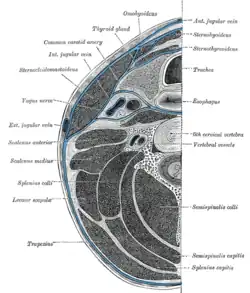

The internal carotid runs vertically upward in the carotid sheath and enters the skull through the carotid canal. During this part of its course, it lies in front of the transverse processes of the upper three cervical vertebrae.

It is relatively superficial at its start, where it is contained in the carotid triangle of the neck, and lies behind and medial to the external carotid, overlapped by the sternocleidomastoid muscle, and covered by the deep fascia, the platysma, and integument: it then passes beneath the parotid gland, being crossed by the hypoglossal nerve, the digastric muscle and the stylohyoid muscle, the occipital artery and the posterior auricular artery. Higher up, it is separated from the external carotid by the styloglossus and stylopharyngeus muscles, the tip of the styloid process and the stylohyoid ligament, the glossopharyngeal nerve and the pharyngeal branch of the vagus nerve. It is in relation, behind, with the longus capitis, the superior cervical ganglion of the sympathetic trunk, and the superior laryngeal nerve; laterally, with the internal jugular vein and vagus nerve, the nerve lying on a plane posterior to the artery; medially, with the pharynx, superior laryngeal nerve, and ascending pharyngeal artery. At the base of the skull the glossopharyngeal, vagus, accessory, and hypoglossal nerves lie between the artery and the internal jugular vein.

Carotid plexus

The sympathetic trunk forms a plexus of nerves around the artery known as the carotid plexus. The internal carotid nerve arises from the superior cervical ganglion, and forms this plexus, which follows the internal carotid into the skull.